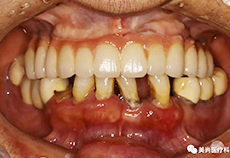

治疗前:下颌牙缺失

治疗前CT照